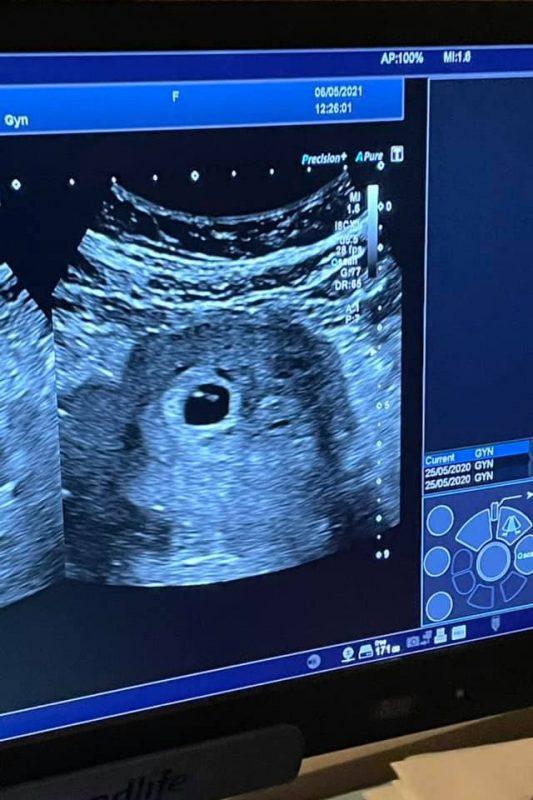

Այսօր ընդունեցինք մեր զոհված զինվորների մայրերից առաջին հղիին…

Հ.Գ.Կոնկրետ դեպքում հղիությունը գրանցվել է առանց բժշկական միջամտության, բայց բոլոր նման ընտանիքների համար գործում է պետական ծրագիր»,- գրել է նա: